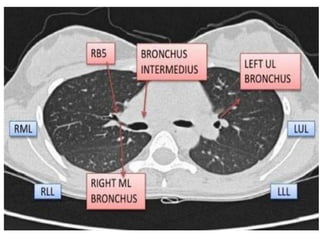

CAÂY PHEÁ QUAÛN VAØ PHAÂN THUØY PHOÅI

+CT cho chi tieát giaûi phaãu toát raát nhieàu so vôùi X

quang qui öôùc

+Phaân tích hình aûnh CT

-Caây pheá quaûn

-Phaân thuøy phoåi

-Raõnh maøng phoåi